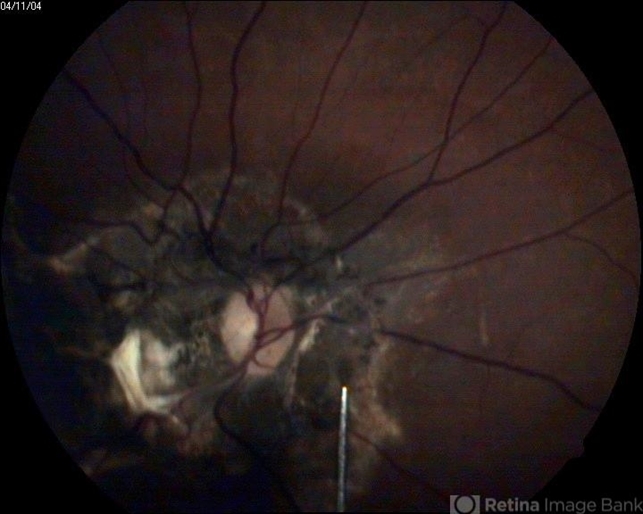

- juxtapapillary subretinal pigmented lesion

- A 23-year-old patient presented to outdoor with loss of vision before three months.On examination his picture was like this.